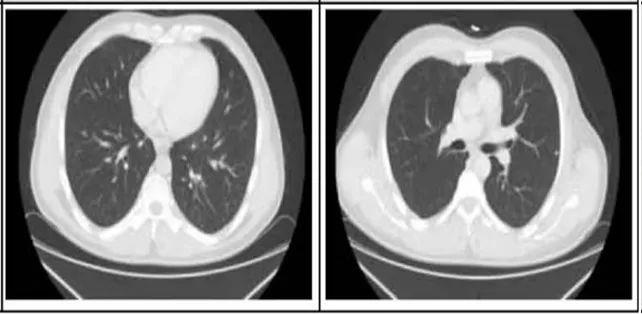

2. 肺部病灶治疗前后核磁对比:

肺部转移病灶在用药后2个月明显缩小,4个月后病灶基本消失。

治疗2个月

治疗4个月

治疗6个月

治疗16个月